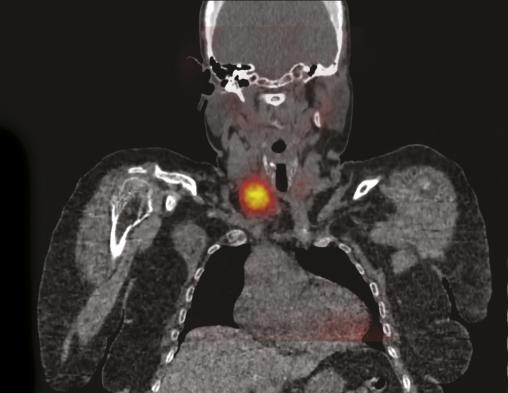

Cette patiente congolaise de 61 ans consultait pour des douleurs lombaires mécaniques anciennes très invalidantes. Les radiographies montraient une déminéralisation osseuse diffuse. La tomodensitométrie du bassin montrait une ostéolyse très particulière des deux sacro-iliaques (fig. 1) ainsi que des lésions fibrokystiques de l’aileron sacré droit (fig. 2). La calcémie était à 3,81 mmol/L, la parathormone était à 1 300 pg/mL (N : 6-50 pg/mL) confirmant le diagnostic d’hyperparathryoïdie primaire. La scintigraphie parathyroïdienne localisait une formation macronodulaire intensément fixante de 30 mm de grand axe au pôle inférieur du lobe thyroïdien droit (fig. 3). La patiente bénéficiait d’une parathyroïdectomie inférieure droite sous anesthésie locale, la calcémie se normalisait en 15 jours et les douleurs s’amélioraient en 3 mois.